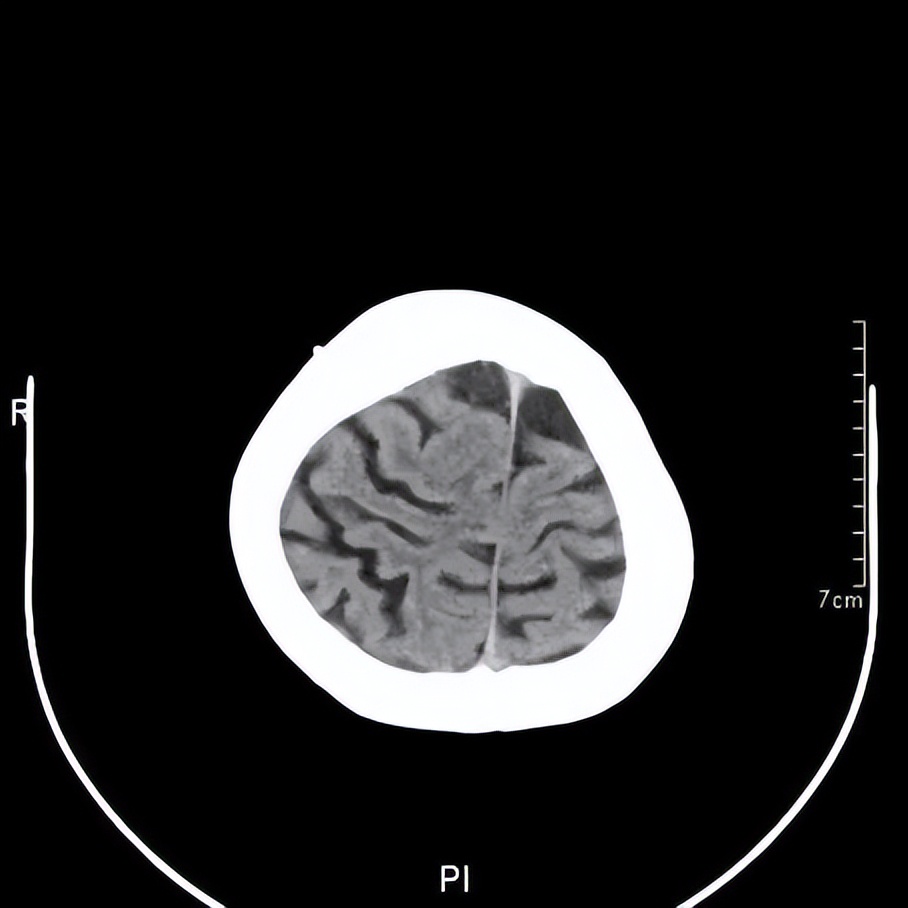

王阿婆术后2月的头颅CT

最终王阿婆在我院神经外科接受了双侧钻孔引流手术。通过几天引流后,她就可以下床走动,说话也清楚了,记忆力也恢复了。她的儿女都很高兴,感谢黄主任和神经外科的医生们。王阿婆出院回家继续休养康复。几个月后复查,血肿完全消退,阿婆又恢复了昔日神采,一家人共享天伦之乐。